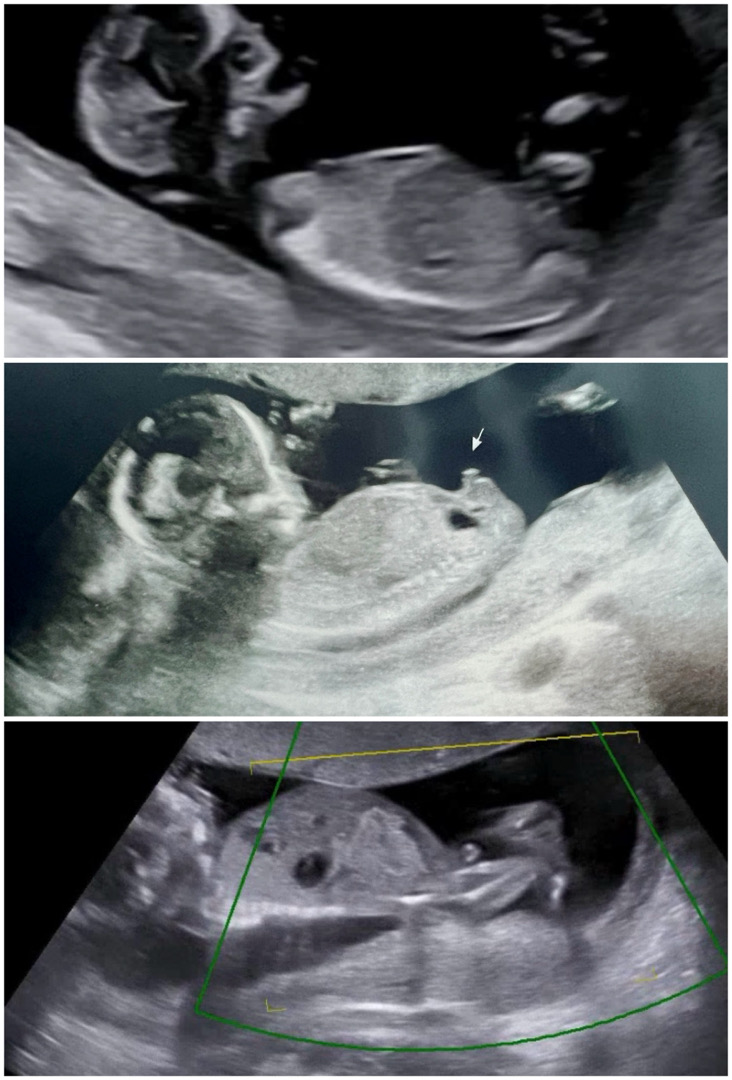

15주 성별 봐주세요 ㅎㅎ

12주차때 각도법 고수님이 딸이라고 해주셧는데 오늘 궁금하서 병원 가니 🌶️갘ㅋㅋㅋㅋㅋㅋㅋㅋㅋㅋㅋㅋ 너무 웃기네요 첫번째 사진이 12주때 두번째 세번째 사진이 15주 입니더!! 성별 확정이겠죠? 젠더리빌 파티하려구요..!!!